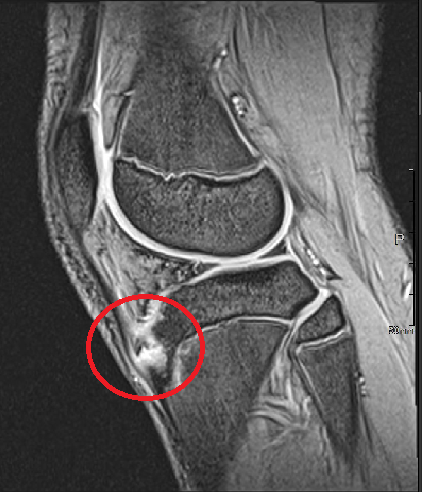

- 診断は、レントゲンやMRI、超音波検査などで行われます。

診断には、レントゲンやMRI、超音波検査などが用いられます。特に、超音波検査は初期段階でも異常を確認しやすいとされています。